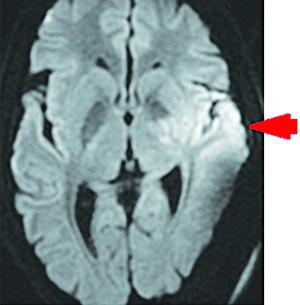

Рисунок 7.Сливные очаги гиперинтенсивного сигнала в области скорлупы, внутренней капсулы, в головке хвостатого ядра и паравентрикулярном белом веществе головного мозга на DWI-режиме.Результаты проведения МРТ головного мозга на 10-е сутки госпитализации (см. рис. 7 и 8). В области скорлупы и внутренней капсулы, в головке хвостатого ядра и паравентрикулярном белом веществе определяются сливные очаги гиперинтенсивного сигнала на Т2FLAIR и DWI, с умеренным ограничением диффузии на ADC, в бороздах мозжечка слева отмечается гиперинтенсивный сигнал на Т2FLAIR. Срединные структуры не смещены. Желудочки мозга не расширены. Субарахноидальные пространства конвекса не изменены. Признаков нарушения ликвородинамики не выявлено.

Рисунок 8.Умеренное ограничение диффузии на ADC-режиме.Базальные цистерны без особенностей. Селлярная область и основание черепа не изменены. Полость турецкого седла не расширена. Гипофиз обычных размеров и формы, контуры ровные, структура однородная. Дифференцировка на нейро- и аденогипофиз сохранена. Мосто-мозжечковые углы свободны, внутренние слуховые проходы не расширены, симметричны.